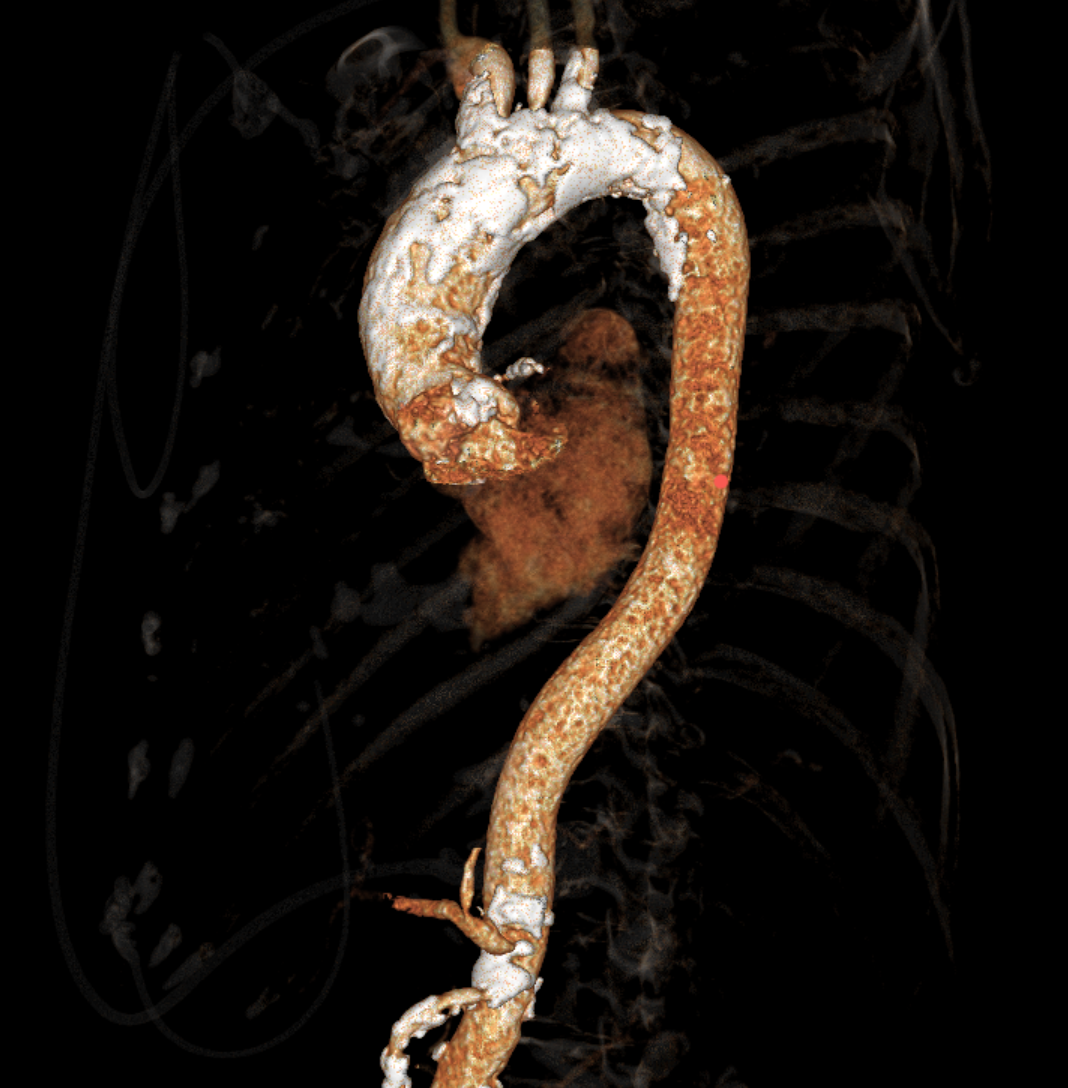

主动脉瓣环周长径21.9mm,小瓣环,LVOT直筒型结构;三叶瓣,左右融合(功能型二叶瓣),瓣叶轻微增厚并重度钙化,钙化主要分布在无冠窦瓣叶边缘及左右交界融合处,瓣上限制较重。

窦部空间适中,STJ内径偏小,升主动脉内径可。

双侧冠脉开口高度可,VTC空间充足,无冠脉风险,双冠内多处钙化,术中评估冠脉支架植入必要性。

左室内径较小,但合并轻度反流,低循环崩溃风险,室间隔膜部长度<3mm,有一定术后起搏器植入风险。

外周双侧入路无明显迂曲、直径可容纳20F大鞘通过,双侧中分叉,穿刺需注意。主动脉弓角弓距可,髂总动脉及分支多处钙化,瓷化升主动脉,钙化由升主动脉蔓延至主动脉弓侧壁及弓顶弓底部,有一定卒中和夹层风险。